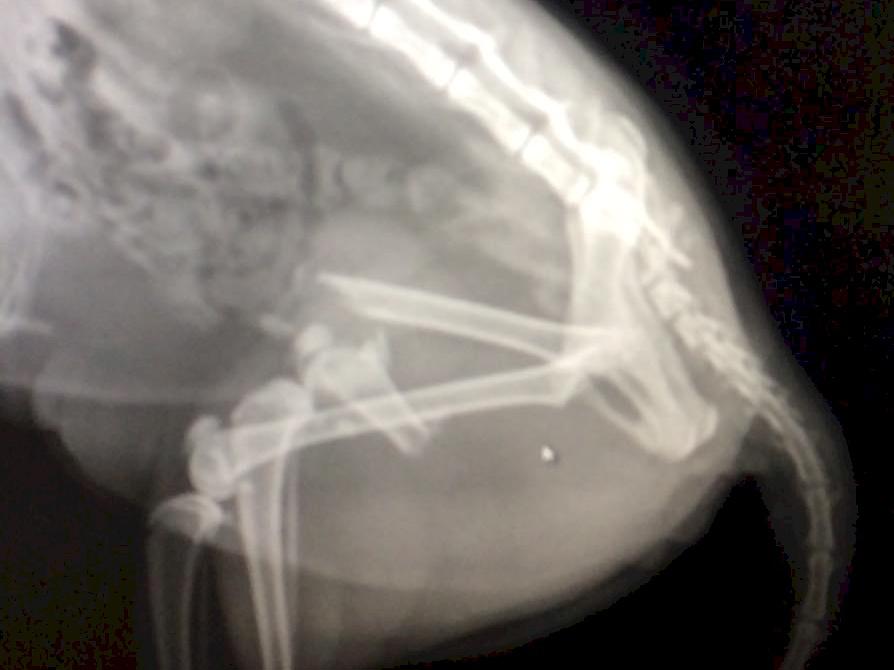

Mr Anderson is my cat. He is one and a half year old. A dog got him the other day so he has an brocken leg and a dislocated tail.

He is a really lively happy cat. I don´t really have the money for the vet. So i had to think about to put him down. I went to see him today at the vet and he still really wants to move around and keep going. So i will try to get the money together. Hope for your support. He is part of our Family and we want to see him grow old. In the operation they will take his tail and pin the leg. He has a chance to be 100% again even without a tail. Thanks so much